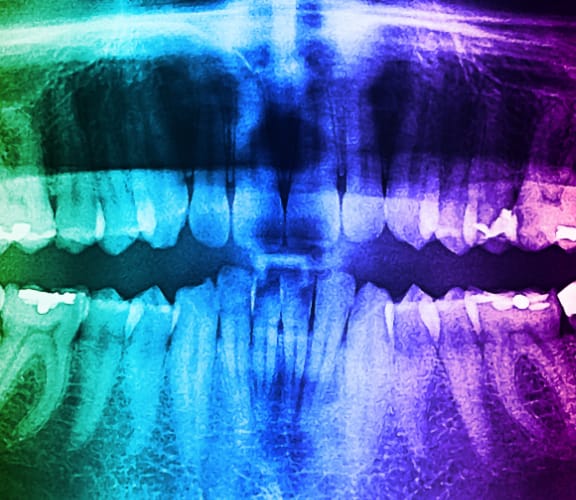

If you need an emergency root canal treatment, we're here to help you. Dr. Reza Madani is available seven days a week to provide you with prompt and effective care. You can expect immediate pain relief and same-day treatment for your dental emergency. Dr. Madani is an expert in his field and will provide you with comprehensive and swift treatment that ensures a healthier, pain-free smile.